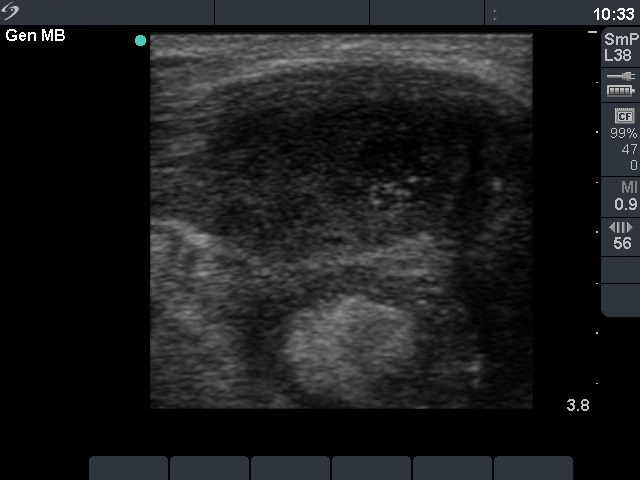

Steroid administration resulted in a prompt amelioration of the clinical symptoms. The steroid was given for 6 weeks in a decreasing dose.

At the time of the discontinuation of steroid therapy (third row):

The size of the lesion was 15x8x19 mm (width x depth x length).